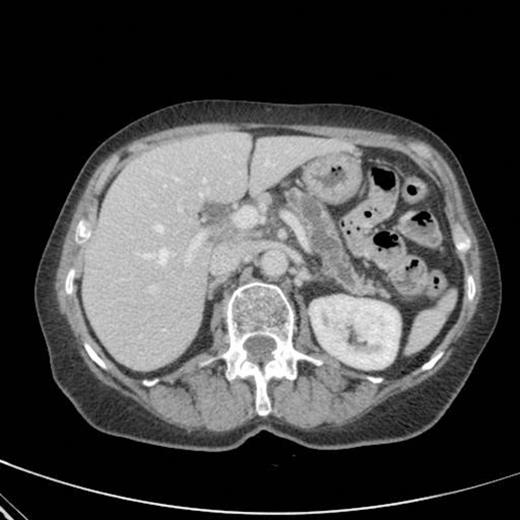

CT scan showing pancreatic duct dilatation to 15 mm with side branch dilatation in uncinate process and atrophic pancreas

CT scan done 2 years later revealed marked dilatation and tortuosity of the main pancreatic duct (12-13mm at the head) with atrophy of the body and tail (Fig1). Repeat scans done on an yearly basis over the next three years reported no progressive change. CT scan done 6 years after the original diagnosis revealed pancreatic duct dilatation to 15 mm with side branch dilatation in uncinate process and atrophic pancreas (Fig 2). A diagnosis of mucinous ductal ectasia or an intraductal papillary mucinous tumour was suggested. On clinical review, patient complained of epigastric discomfort, loose stools, anorexia and weight loss. Upper GI endoscopy and colonoscopy was normal. Faecal elastase was less than 100 confirming pancreatic insufficiency for which she was commenced on creon.